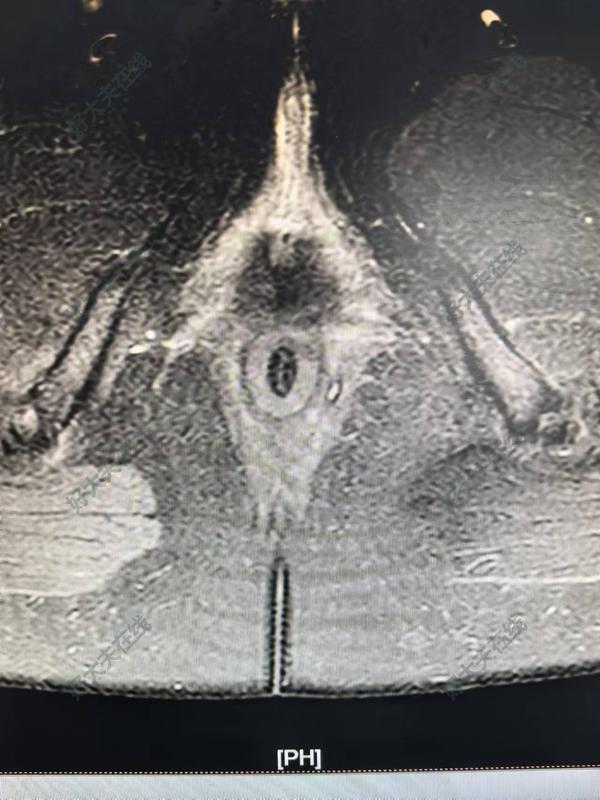

治療前患者男,50歲,反復(fù)肛門腫痛10年,4個月前在外院行肛瘺手術(shù)治療,術(shù)后癥狀反復(fù),伴肛旁流膿水。治療中術(shù)前磁共振檢查提示左側(cè)括約肌上瘺(內(nèi)口位于12點。沿12點肌間蔓延至DPIS間隙,向后突破部分恥骨直腸肌,突破左側(cè)恥骨直腸肌,向下經(jīng)左側(cè)坐骨直腸間隙至左側(cè)肛周皮膚)治療后治療后即刻對于復(fù)雜性肛瘺,術(shù)前必須明確診斷,強烈建議磁共振檢查!??!千萬不要按照傳統(tǒng)方法,術(shù)中“亂切亂捅”,治療過度不僅造成肛門不可逆損傷(門診見到太多這樣的患者了,很無奈?。?,而且加重術(shù)后疼痛。治療不徹底又會造成像該例患者高位感染間隙遺漏的情況。在肛門這塊寸土寸金的地方,本人始終堅持肛門功能的保護(hù)是治愈的前提?。?!這位患者采用TROPIS+Parks松弛掛線,不僅最大限度降低了損傷,保護(hù)了肛門功能,同時術(shù)后疼痛非常?。ɑ颊哂H訴)。一切源于精準(zhǔn)治療?。。?/p>